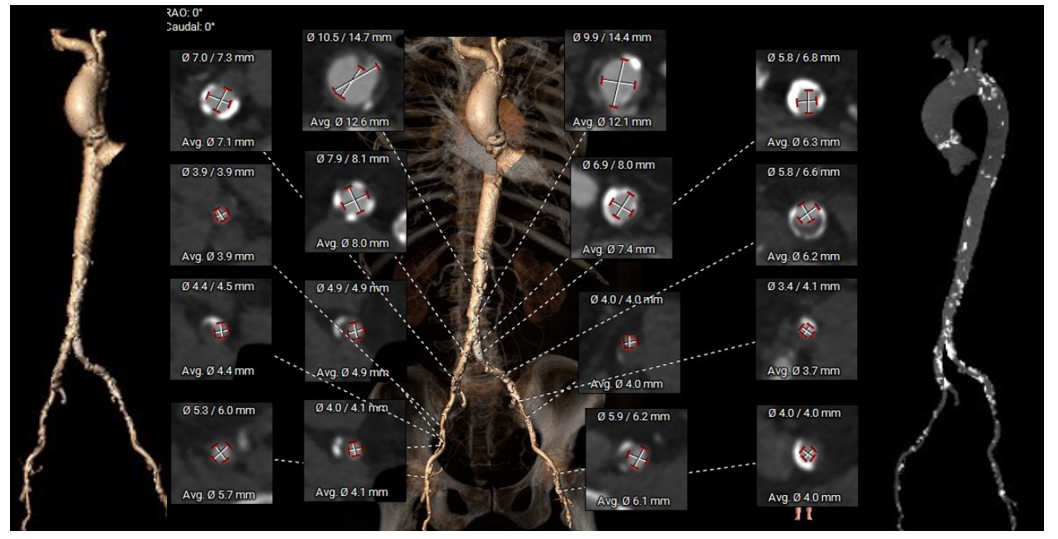

外周血管及主动脉弓解剖:

弓部及入路评估: